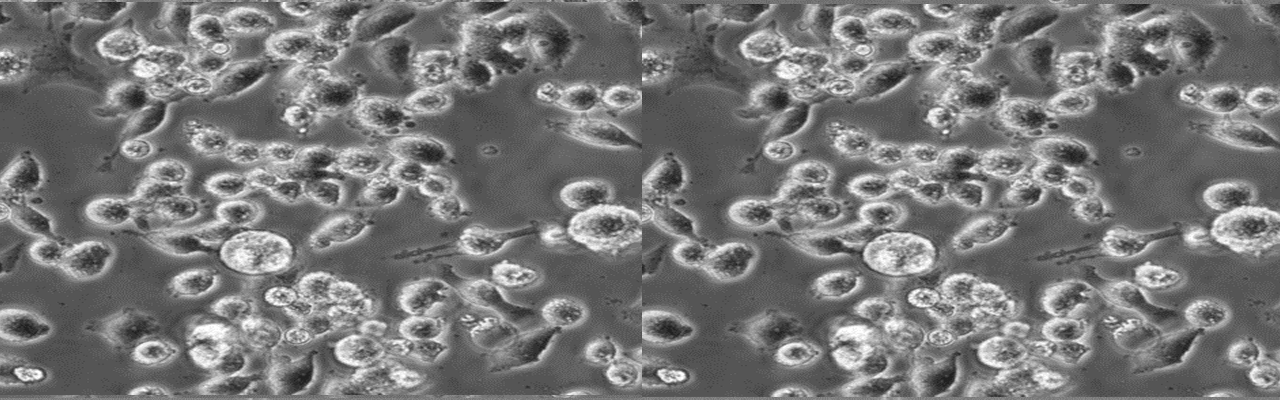

| 名称 | MIA PaCa-2 |

| 细胞全名 | 人胰腺导管癌细胞 |

| 生长特性: | 悬浮聚集 |